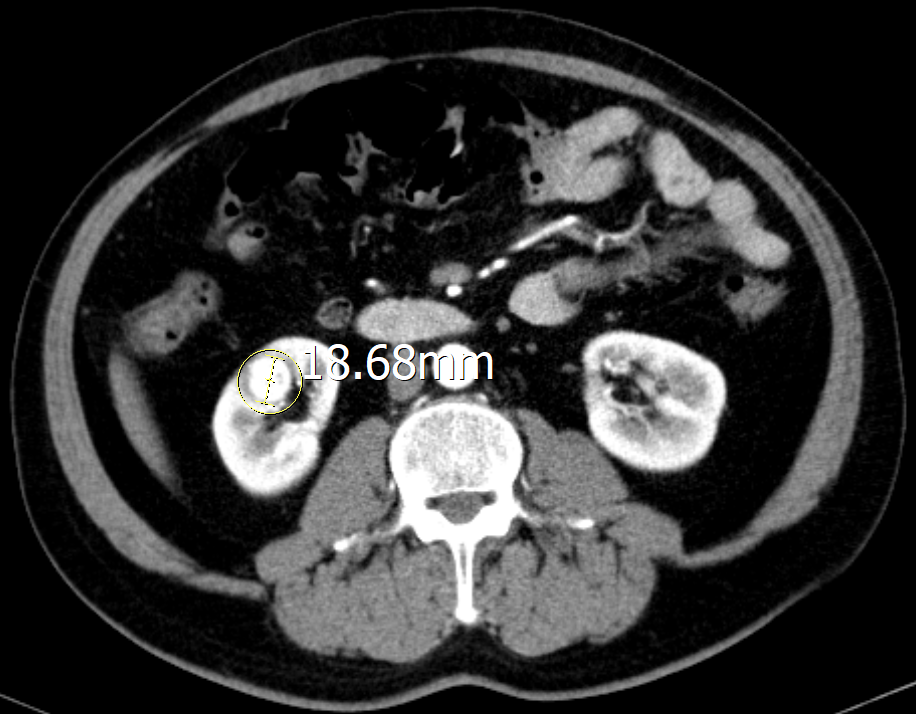

“结合相关影像资料,我们发现患者右肾皮质内见类圆形强化灶,直径约18mm,边界模糊不清,考虑恶性肿瘤。建议开展手术。”泌尿外科主任李胜文表示。

由于胡大爷的肾肿瘤隐匿于肾实质深处,被正常肾脏组织包裹,手术中肉眼无法观测,定位非常困难,肿瘤位置判断不准确,可能导致⼿术不彻底或损伤周围健康组织,因此必须借助其他⼿段辅助定位